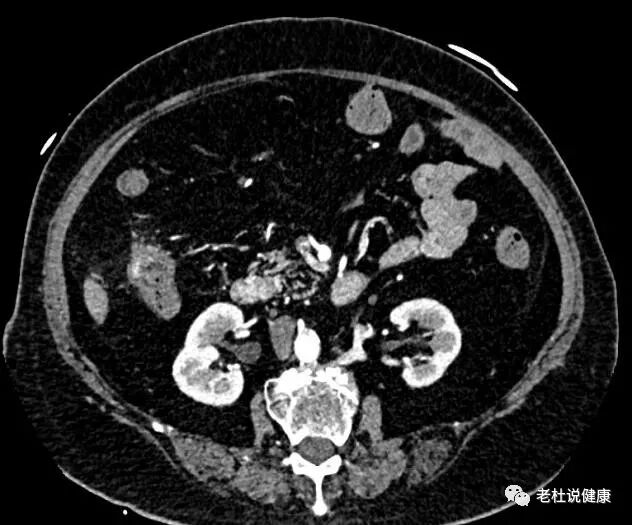

接诊医生安排做了腹部平扫CT、和腹部血管成像检查,结果发现老太太的结肠肝区肠壁明显增厚,周围渗出性改变,腹部多处血管严重狭窄;

结肠肝区肠壁明显增厚,周围渗出性改变